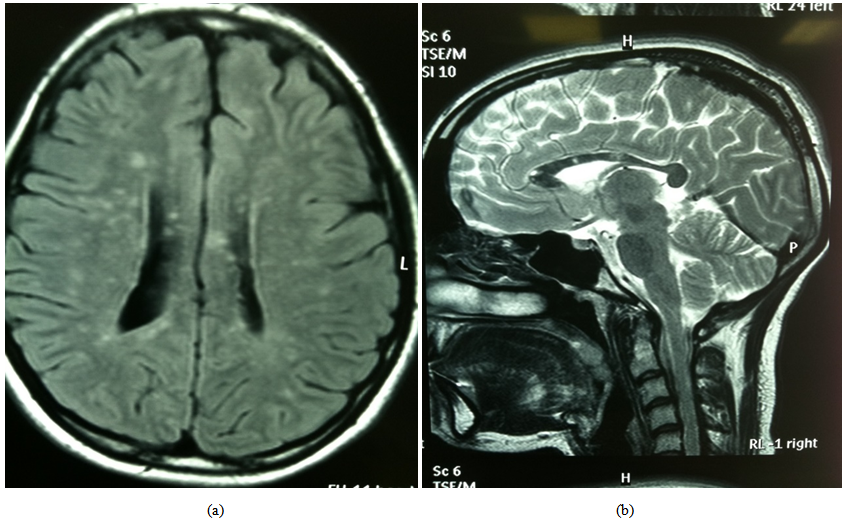

43 Year Old Female With Susac Syndrome Characterised By The Clinical Download Scientific Diagram